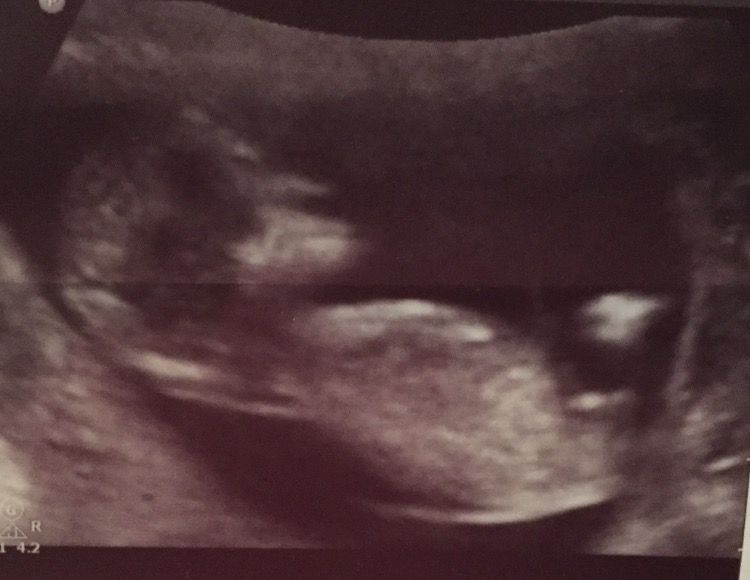

Maybe girl but more pics would help :)